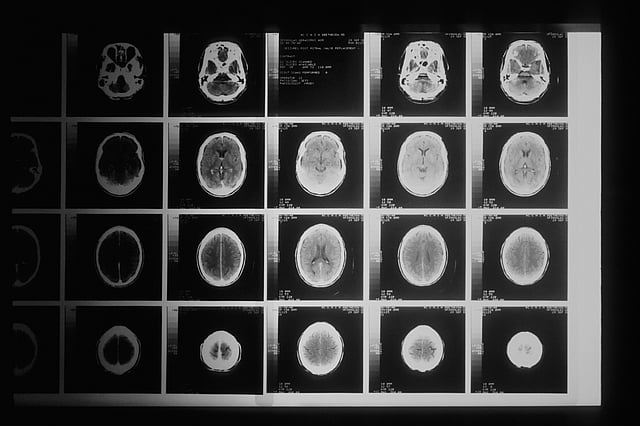

"Over a series of MRI scans, I watched as the tumour completely disappeared," Grill told AFP.